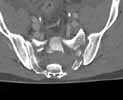

In 1991, I treated an obese patient with similar "traumatic upper sacral spondyloptosis" and placed him into a spica cast for several reasons...over 6 weeks being supine or log-rolled in the cast, he reduced ~80+% normal (surprisingly) and maintained his neurological status...maybe he was/we were just lucky, but the reduction was impressive...I'll include his injury and follow up slides.

Example case - Click to Magnify